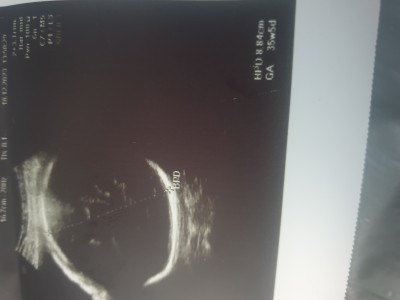

Kizlar seker yuklemesi yaptrmamistim bbek iri dendi havtasina gore ultrason resmi altta bas bolgesi ileride gorunuyor bu sikintimi 33+2 günlük regle gore  yarinda seker yuklemesi yptrcam 100 luk yazmış doktor bu fazlami sizce

Teşekkür ederim kafasi niye ilerde cikmis onu anlamadım doktorda birsey demedi

(1,990 puan) tarafından

Kafa kaç hafta ilerde iki hafta ilerde olması yada geride olmasi sorun olmuyor ilerde demek  kafası yapısı biraz  büyük demek canim benim bebeğimde öyledi genetik yapı anne yada babanin kafası biraz büyükse bebeğinde büyük olabiliyor o yüzden ilerde çıkabilir genetik yani :)